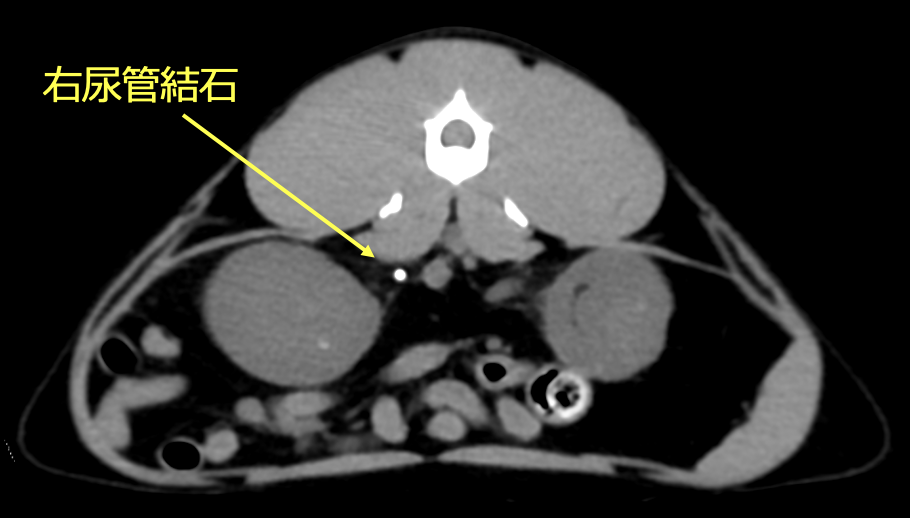

レントゲン、CT検査より左右の尿管に結石が認められた。また左腎臓腎盂の拡張が認められた。

左右尿管結石と診断した。治療は、腎臓の数値を下げるため、まずは腎瘻チューブを設置した。腎数値に改善が認められないので、開腹にて尿管膀胱側側吻合術を行った。